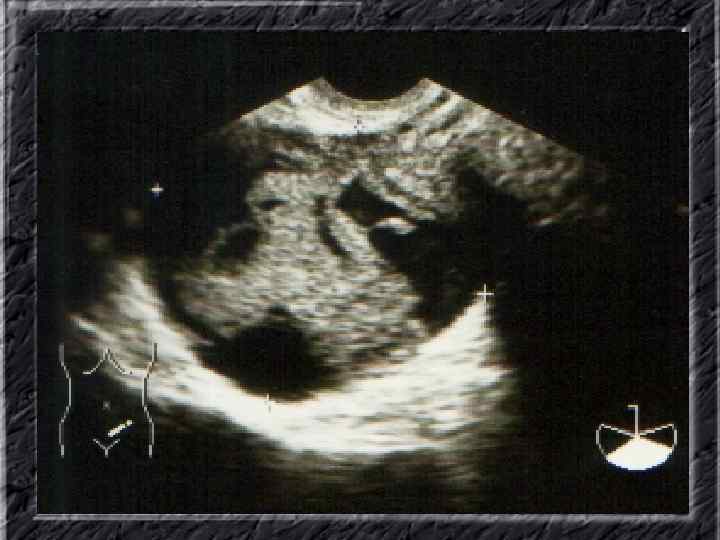

Названия слайдов: • • • • Слайд 61. Лапароскопия: множественные спайки в полости малого таза женщины. Слайд 62. Лапароскопия: признаки спаечной болезни в полости малого таза женщины. Слайд 63. Лапароскопия: деформация маточной трубы при спаечном процессе в полости малого таза. Слайд 64. Ультрасонография: спаечный процесс в малом тазу. Слайд 65. Ультрасонография: мультифолликулярные яичники. Слайд 66. Ультрасонография: кистома яичника. Слайд 67. Ультрасонография: патолоргия эндометрия. Слайд 68. Ультрасонография: внематочная беременность. Слайд 69. Ультрасонография: внематочная беременность. Слайд 70. Кольпоскопия: кандлилома – папиллома. Слайд 71. Кольпоскопия: кандлидозные бели. Слайд 72. Кольпоскопия: полип шейки матки. Слайд 73. Кольпоскопия: эрозия шейки матки. Слайд 74. Кольпоскопия: экспульсия ВМС.